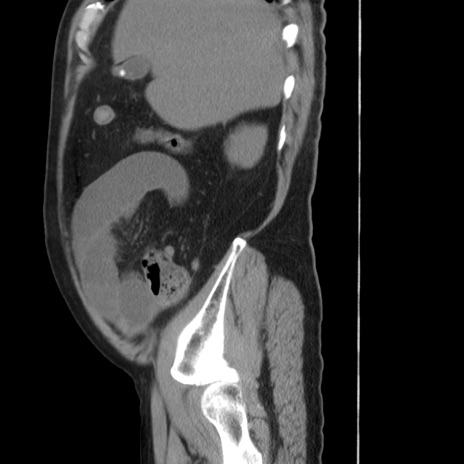

症例20(矢状断像)

【症例】 60歳代男性

【主訴】 腹部膨満、嘔吐

【現病歴】5日前頃より倦怠感を認め食事量減少し4日前の朝嘔吐、食事摂取困難となった。 3日前近医受診し点滴施行され整腸剤などを処方された。 当日他院を受診し、腹部膨満著明、炎症反応の上昇(CRP10.8、WBC11200)あり、紹介受診となる。

【身体所見】 意識JCS1 受け答えがはっきりしないBP 111/57mHg、 P 67bpm、、BT35.2°C、SpO2 97%(RA)、 腹部:膨隆、打診で鼓音あり、全体的に圧痛有り、腸蠕動音(-)、反跳痛ははっきりせず。

【データ】WBC 11400、CRP 14.20